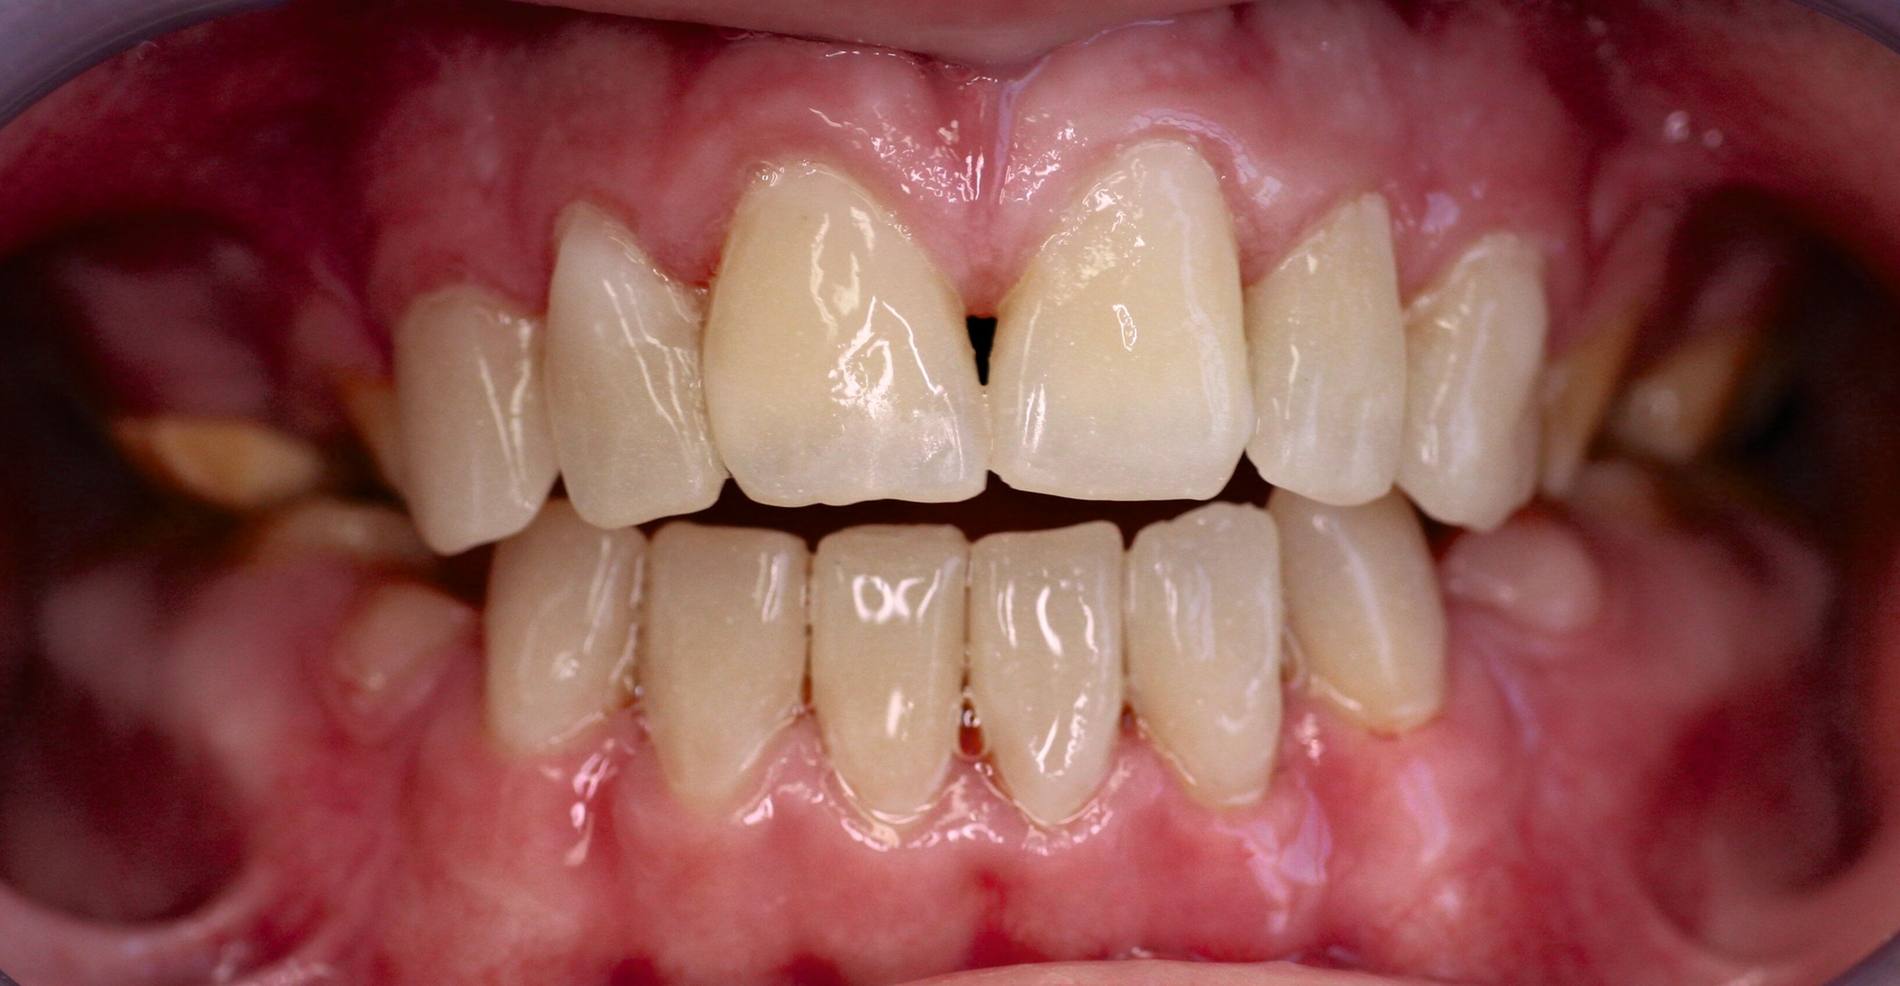

Klinisch zeigten sich ein nicht-kariöses Wechselgebiss mit generalisierter Schmelzhypoplasie an allen Zähnen sowie eine insuffiziente Mundhygiene. Zusätzlich bestanden eine fehlende Mittellinienübereinstimmung, ein Overbite von minus vier Millimetern und ein Overjet von sechs Millimetern (Abbildung 5), die sich phonetisch in einem interdentalen Sigmatismus äußerten. Röntgenologisch waren alle Zähne angelegt, jedoch war der Zahnschmelz stark reduziert oder vollständig fehlend (Abbildung 6).

Die restaurative Versorgung erfolgte in zwei Phasen: Die Frontzähne wurden im Jahr 2018 (Abbildungen 7 und 8), die Seitenzähne im Jahr 2023 behandelt (Abbildungen 9 bis 12). Im Jahr 2018 fiel die Therapieentscheidung auf indirekte Restaurationen, da eine mangelnde Adhärenz des Patienten vorlag, die sich in geringer Geduld für längere Sitzungen äußerte. Zudem war über einen längeren Zeitraum keine zuverlässige Trockenlegung möglich. Durch diese Vorgehensweise konnten die Anzahl und die Dauer der Behandlungstermine reduziert werden.

Die Therapie begann mit einer PZR und der Anfertigung eines diagnostischen Wax-ups auf Situationsmodellen. Dieses wurde in PMMA (PalaVeneer Dentine, Kulzer) umgesetzt. Nach Reinigung der Frontzähne mit Bürstchen und fluoridfreier Polierpaste erfolgte die Anprobe der Kronen. Anschließend wurden die Kronen nach Konditionierung (Clearfil SE Bond, Kuraray Dental) mit einem Befestigungskomposit (Variolink Esthetic DC, Ivoclar Vivadent) unter relativer Trockenlegung mittels Watterollen, Speichelschnecke und Sauger definitiv eingegliedert.

Die zu diesem Zeitpunkt seit fünf Jahren inserierten Frontzahnkronen zeigten Randverfärbungen sowie durch den Durchbruch entstandene Stufen zur natürlichen Zahnhartsubstanz (Abbildung 9). Diese wurden durch Sandstrahlen (CoJet, Solventum), anschließende Konditionierung mit einem Drei-Schritt-Etch-and-Rinse-System und Komposit (Filtek Supreme, Solventum; Tetric EvoFlow, Ivoclar Vivadent) korrigiert und abschließend poliert.